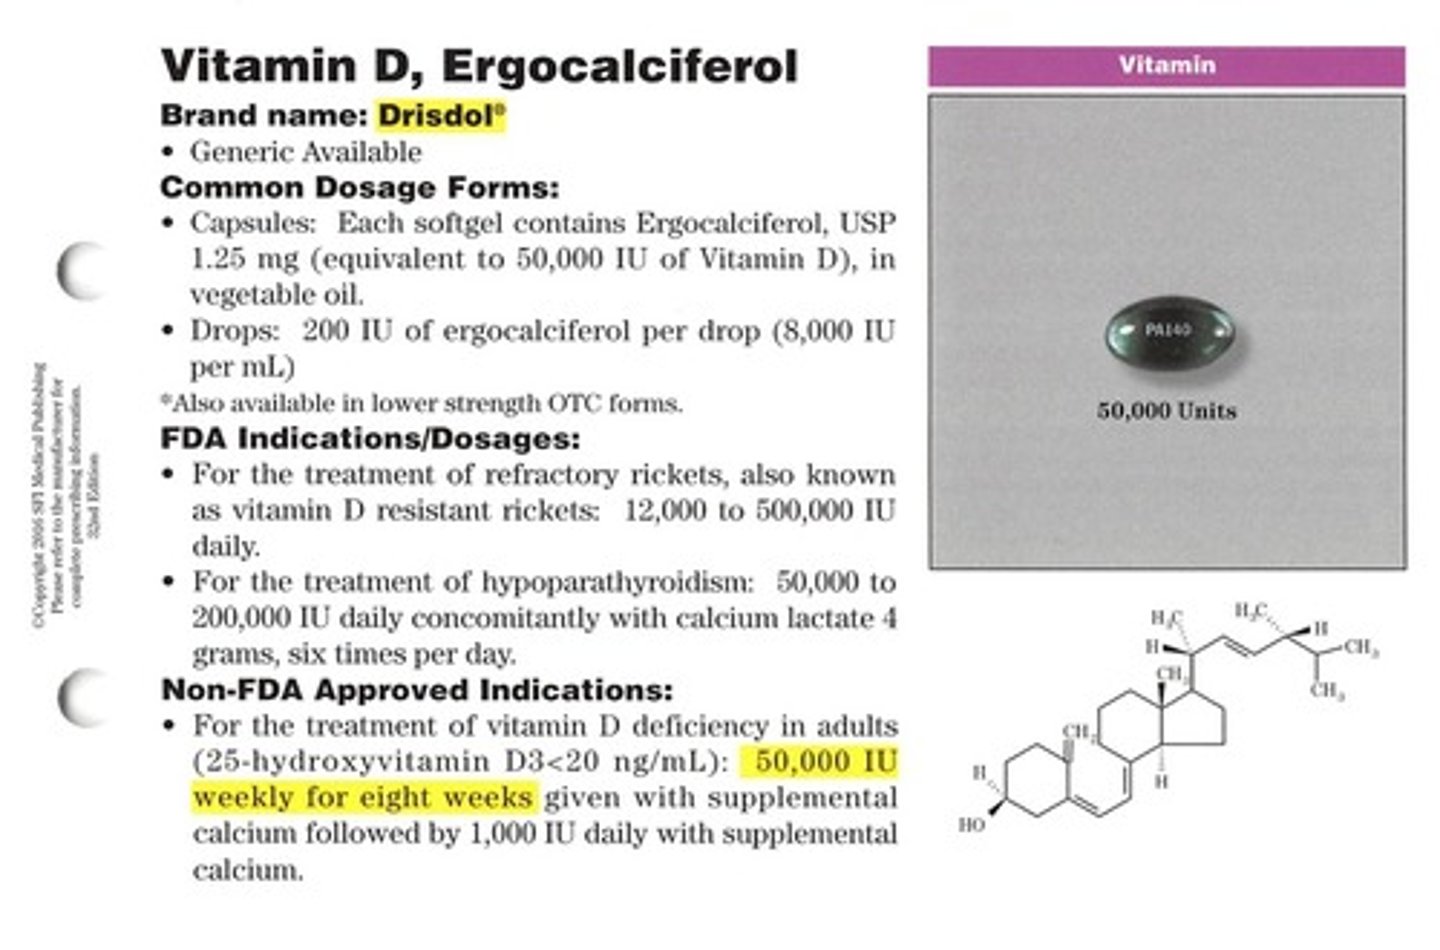

Ergocalciferol

Brand: Deltalin

Class: Vitamin D Supplement

Indication: Vitamin D Supplement

Schedule: NCLM